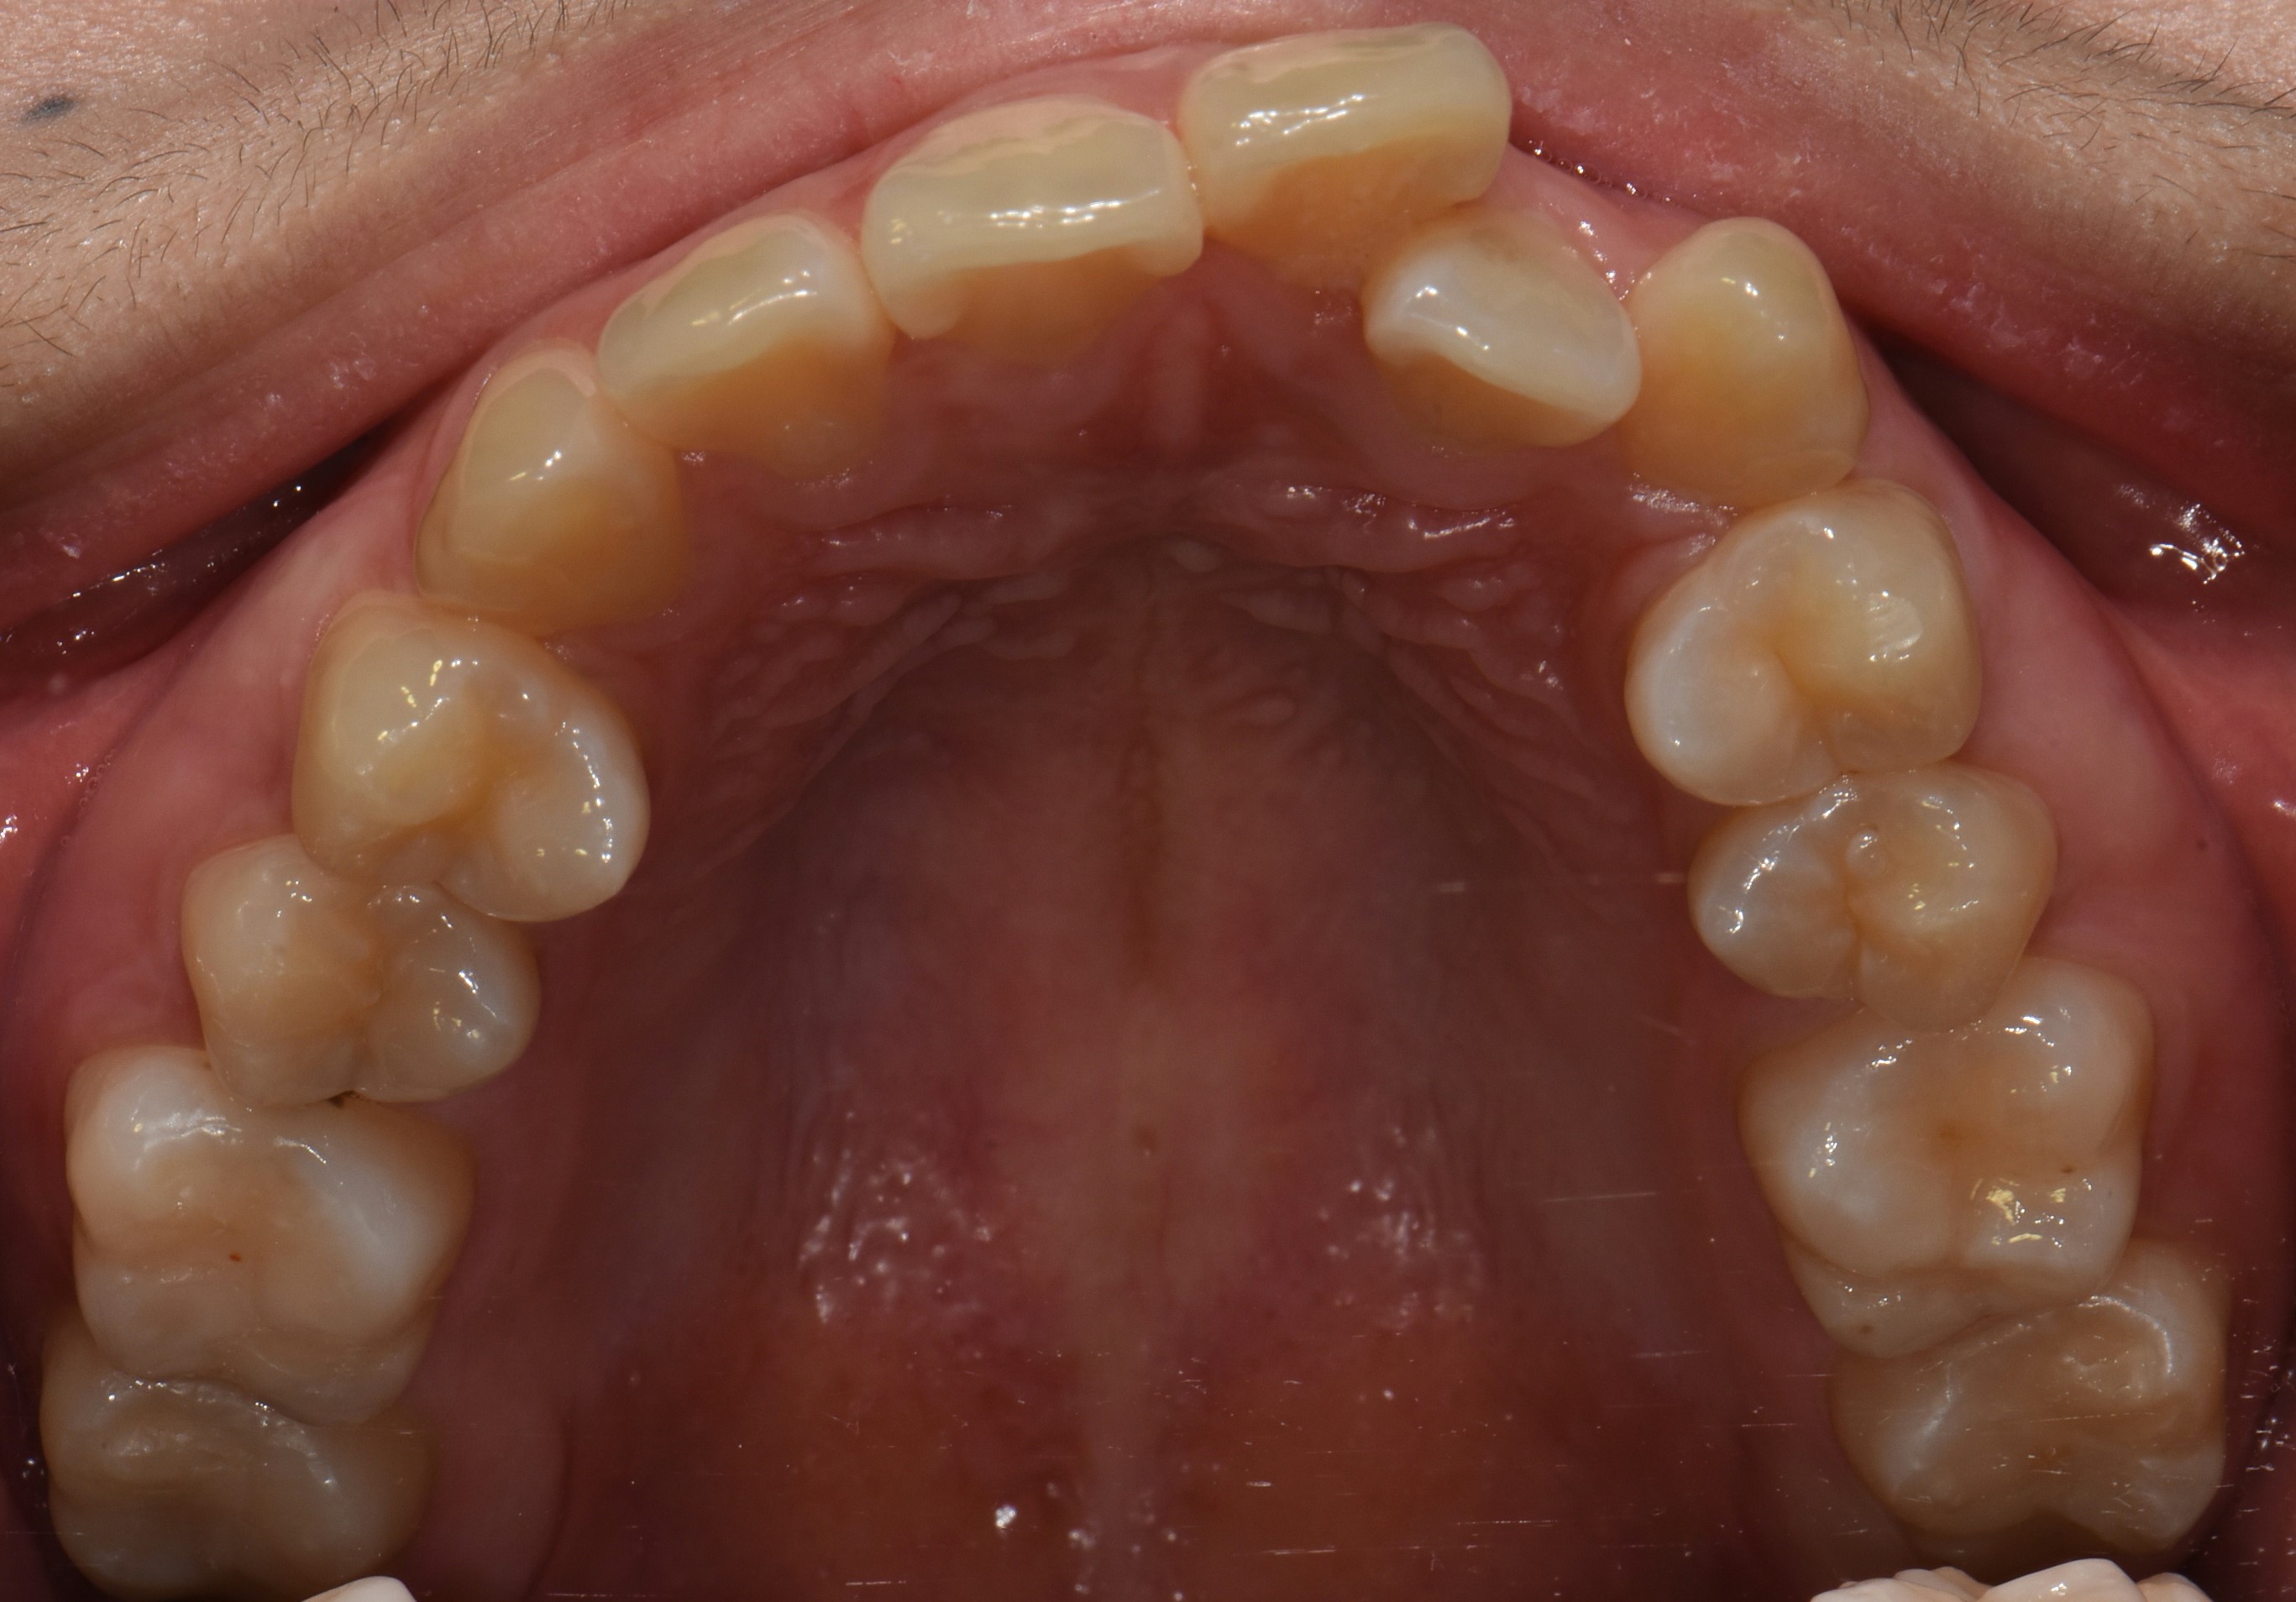

치료 전 사진입니다.